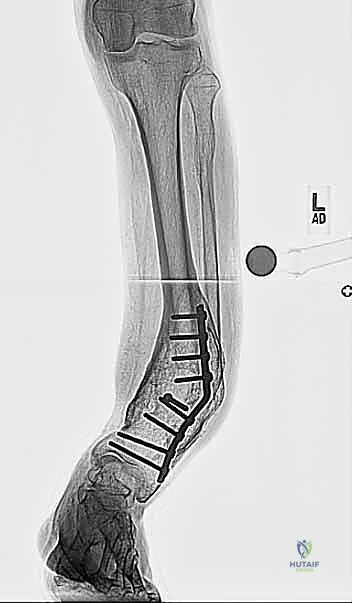

| وجه المقارنة | العلاج التحفظي (بدون جراحة) | الجراحة بالتثبيت الداخلي (شرائح ومسامير) | الجراحة بالتثبيت الخارجي (طريقة د. هطيف المفضلة للتشوهات المعقدة) |

| آلية العلاج | أحذية طبية، دعامات، علاج طبيعي ومسكنات. | قطع العظم وتثبيته فوراً في الوضع الصحيح باستخدام شريحة معدنية داخلية. | قطع العظم وتركيب هيكل معدني خارجي متصل بالعظم بأسلاك، مع تصحيح تدريجي. |

| القدرة على تصحيح التشوهات | لا يصحح التشوه، بل يخفف الأعراض مؤقتاً فقط. | ممتاز للتشوهات البسيطة وذات البعد الواحد (مثل التقوس فقط). | استثنائي. يصحح التشوهات المعقدة، ثلاثية الأبعاد، ويعالج قصر الساق في نفس الوقت. |

| التأثير على الأنسجة الرخوة (الجلد) | لا يوجد تأثير. | يتطلب شقاً جراحياً كبيراً، مما قد يسبب مشاكل في التئام الجرح، خاصة إذا كان الجلد متضرراً مسبقاً. | أقل تدخل جراحي. يتم عبر ثقوب صغيرة، مما يحمي الجلد والأنسجة الرخوة والأوعية الدموية. |

| القدرة على تعديل التصحيح بعد الجراحة | غير ممكن. | غير ممكن. إذا كان هناك خطأ، يتطلب جراحة أخرى. | ميزة حصرية. يمكن تعديل زوايا التصحيح يومياً في العيادة دون تخدير حتى الوصول للمثالية. |

| التحميل والمشي | مسموح. | يمنع المشي على الساق لعدة أسابيع أو أشهر حتى يلتئم العظم. | مسموح مبكراً. المريض يشجع على المشي والتحميل الجزئي على المثبت الخارجي، مما يسرع بناء العظم. |

كما يوضح الجدول، يتفوق التثبيت الخارجي في الحالات المعقدة، حالات ضعف الأنسجة الرخوة، وحالات قصر الأطراف المترافقة مع التشوه.